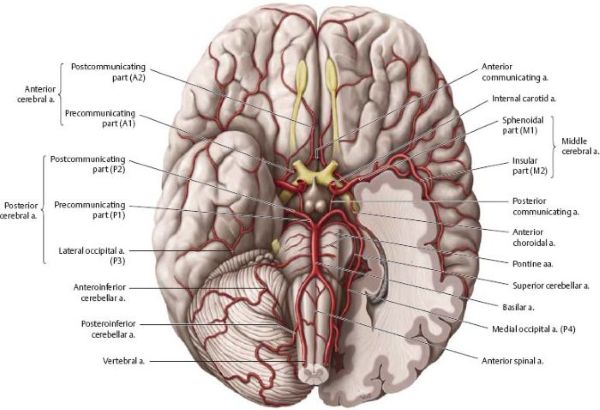

ხერხემლის არტერია (VA), რომელიც ჩვეულებრივ იწყება ლავიწქვეშა არტერიიდან (მარჯვენა - მხარ-თავის ღეროდან, მარცხენა - პირდაპირ ლავიწქვეშა არტერიიდან), იყოფა ოთხ ანატომიურ სეგმენტად[1, 2]:

V4 სეგმენტიდან გამოდის მნიშვნელოვანი ტოტები, მათ შორის მცირე შეღწევადი არტერიები, რომლებიც კვებავენ მოგრძო ტვინს და, რაც მთავარია, ნათხემის ქვედა უკანა არტერია (PICA) [1, 2]. PICA ჩვეულებრივ იწყება დისტალური V4 სეგმენტიდან, მარყუჟს აკეთებს მოგრძო ტვინის გარშემო (კვებავს მის ლატერალურ ზედაპირს) და შემდეგ სისხლით ამარაგებს ნათხემის ქვედა ზედაპირს და მეოთხე პარკუჭის ქოროიდულ წნულს [1, 2]. PICA-ს საწყისსა და მომარაგების არეალში არსებობს მნიშვნელოვანი ანატომიური ვარიაციები [1, 2].

კოლატერალური სისხლმომარაგება შეიძლება განხორციელდეს V2 სეგმენტის კუნთოვან ტოტებსა და გარეთა საძილე არტერიის (მაგ., კეფის არტერია) ან ფარისებრ-კისრის ღეროს (მაგ., კისრის ასწვრივი არტერია) ტოტებს შორის არსებული ანასტომოზების მეშვეობით [1]. ხერხემლის არტერიის ჰიპოპლაზია (განუვითარებლობა) ხშირია (დაახლოებით 10%), რაც კონტრალატერალურ ხერხემლის არტერიას და კოლატერალურ გზებს კრიტიკულად მნიშვნელოვანს ხდის დომინანტური ხერხემლის არტერიის ოკლუზიის შემთხვევაში [1].